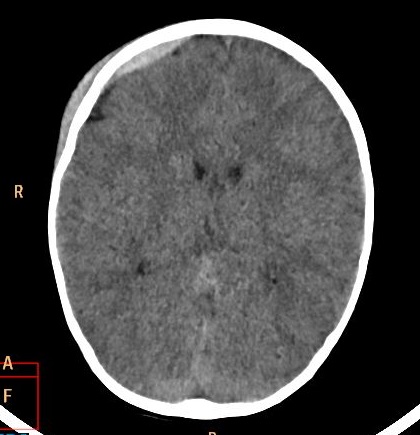

Przypadek 11: 2-letnia dziewczynka, siedziała zapięta w foteliku na rowerze. Rower upadł razem z pacjentką, dziewczynka nie miała kasku. Nie straciła przytomności. Po urazie kilkakrotnie wymiotowała. Badanie TK głowy.

Rozpoznanie: W tomografii komputerowej uwidoczniono krwiak nadtwardówkowy o wym. ok. 40x6mm w prawej okolicy czołowej. Poza tym mózgowie bez widocznych zmian ogniskowych w badaniu jednofazowym, bez cech uogólnionego obrzęku. Struktury pośrodkowe nieprzemieszczone.Kości czaszki bez zmian pourazowych.